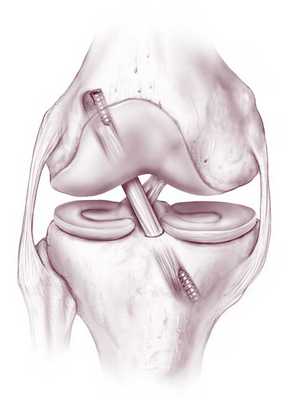

Артроскопическая пластика передней крестообразной связки коленного сустава

· первым этапом выполняется диагностическая артроскопия сустава, устанавливается характер поражения связок, сопутствующие проблемы с менисками, хрящом. При реконструкции передней крестообразной связки выполняется замещение поврежденной связки аутотрансплантатом. Для этого при помощи кусачек, артрошейвера (расходный материал - лезвие шейвера), артроскопического электрода (расходный материал - электрод) производится вапоризация и удаляются остатки поврежденной связки;

· при помощи специального инструмента в области «гусиной лапки» выполняется забор аутотрансплантатов сухожилий подколенных мышц (полусухожильная и нежная), по специальной технике формируется аутотрансплантат ПКС (расходный материал - полиэтиленовая плетеная нить - 2 шт.). Либо соответствующим способом производится забор другого вида аутотрансплантата (из сухожилия прямой мышцы бедра с или без костного блока, из связки надколенника с костными блоками) с формированием из них аутотрансплантата. Либо используется синтетический или аллотрансплантат;

· далее в соответствие с диаметром аутотрансплантата в бедренной и большеберцовой костях формируются каналы, в которые заводится аутотрансплантат. Формирование каналов выполняется при помощи специальных направителей бедренный и тибиальный таким образом, чтобы повторить геометрию нативной ПКС. В латеральном мыщелке бедренной кости формирование канала выполняется по спице диаметром 4 мм (расходный материал), при этом проведение направляющей спицы предпочтительно через антеромедиальный доступ, в большеберцовой кости по спице диаметром 2,4 мм (расходный материал). Подготовленный аутотрансплантат через тоннель большеберцовой кости заводится в тоннель бедренной кости. Фиксация на бедре кортикальная при помощи металлического или биологического фиксатора за мыщелок бедра (расходный материал) или иным фиксатором или способом (другие виды экстракортикального, внутриканального фиксатора), в тоннеле большеберцовой кости фиксация выполняется при помощи биокомпозитного винта (расходный материал) или иным фиксатором или способом (другие виды экстракортикального, внутриканального фиксатора).

Операция на ПКС: виды пластики, принцип выполнения

Любая пластическая процедура на ПКС в настоящий момент выполняется методом малоинвазивной артроскопии. Артроскопический сеанс проходит закрытым способом под спинномозговой анестезией. Операция относится к щадящему типу хирургии высокой точности, поэтому мягким тканям, нервным и сосудистым образованиям не причиняется ущерб. Кроме того, манипуляции проводятся сугубо на пострадавшем участке, а после вмешательства никаких рубцов и шрамов не остается.

Чтобы осуществить реконструкцию поврежденного элемента, достаточно сделать один 5-мм прокол для оптического зонда, в который встроена миниатюрная видеокамера, и 1-2 дополнительных доступа (не более 8 мм в диаметре). Через вспомогательные отверстия хирург микрохирургическими инструментами будет заниматься воссозданием испорченной области. Зрительный контроль обеспечивает артроскоп (эндоскопический зонд), который выводит изображение оперируемой зоны на монитор в 40-60-кратном увеличении. Оперативное вмешательство может быть выполнено несколькими способами, рассмотрим их дальше.

Аутотрансплантация

В данном случае пересаживается фрагмент сухожилий пациента, взятый из мышц бедра, иногда берут материал из связок или сухожилий надколенника. На функциональности донорского участка это никак не отражается. Техника выполнения реконструкции заключается в удалении разорванных связочных структур с последующим внедрением на их место подготовленного трансплантата из сухожилий.

Зона «забора» материала.

Концевые участки сухожильного лоскута вдеваются в просверленные каналы бедренной и большеберцовой кости и натягиваются до нужных параметров, после чего закрепляются биоразлагаемыми винтами либо садятся на специальные петли. Через несколько месяцев без проблем происходит их полное врастание в кость. Методика хорошо изучена и имеет внушительную доказательную базу эффективности, поэтому является на сегодняшний день самой применяемой тактикой лечения ПКС, «золотым стандартом» ортопедии и травматологии.

Пластика по методу «Легамис»

Для реконструкции берется специальный имплантат, представляющий собой полиэтиленовую нить и гипоаллергенную стальную втулку. Нить фиксируется к кости бедра, втулка устанавливается в кость голени. Синтетическая нить протягивается вдоль проблемной связки, соединяя ее разорванные части, а затем в оптимальном натяжении соединяется с концом втулки.

Таким образом, достигается надежная стабилизация колена, за счет чего создаются благоприятные условия для естественного сращения разрыва. Метод целесообразен только при свежей травме, давностью не более 3 недель. На сегодняшний день данный способ практикуется в единичных клиниках Европы, как правило, в медицинских центрах Германии. Собственно, немецкими специалистами эта технология и была разработана.